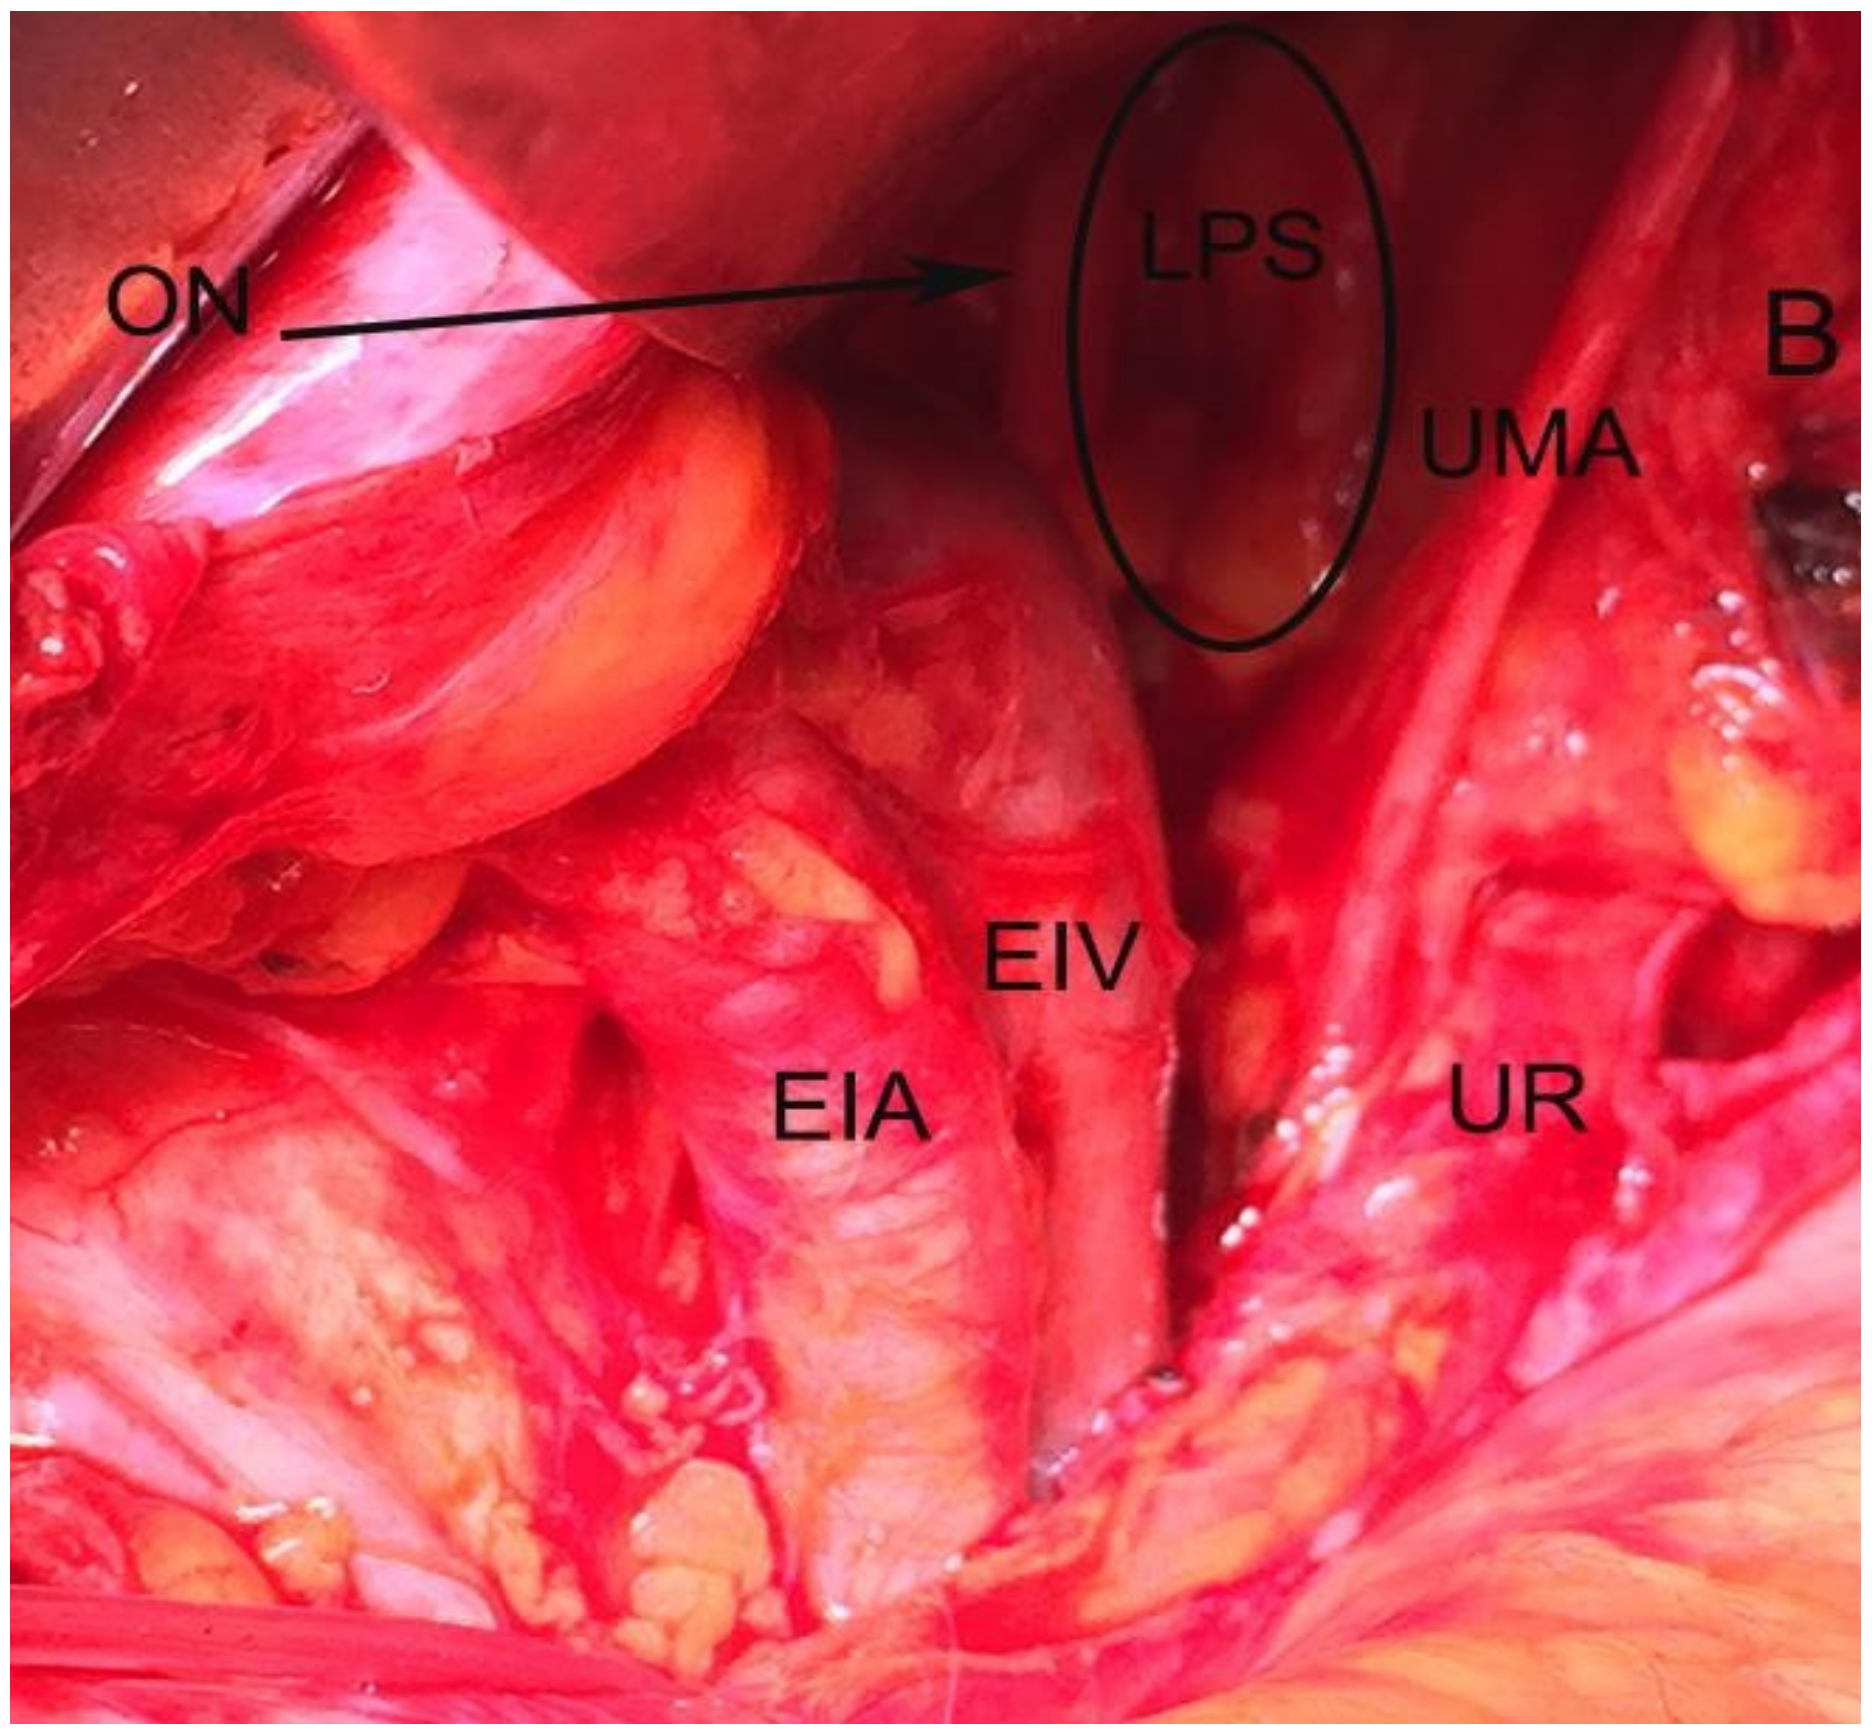

Figure 4. Lateral paravesical space dissected by open surgery (left side of the pelvis). LPS—lateral paravesical space; ON—obturator nerve; UMA—obliterated umbilical artery; UR—ureter; EIV— external iliac vein; EIA—external iliac artery; B—bladder.

The space within the LPS is known as obturator space. This space has the same boundaries as the paravesical space, except for a medially–superior vesical artery. The obturator space contains an obturator nerve/artery/vein, loose areolar, and lymphatic tissue [8]. The paravesical space is dissected by transecting the round ligament and cutting the anterior leaf of broad ligament ventrally and laterally to the obliterated umbilical artery [5]. Transecting the round ligament is not a necessary step. In our opinion, it is not necessary to transect the round ligament when performing laparoscopic pelvic lymphadenectomy previous to radical hysterectomy. The obliterated umbilical artery is identified and after ventral dissection, the paravesical space is opened to the level of levator ani muscle for the MPS and obturator nerve for LPS, respectively [5,7,9]. LPS and MPS can be dissected through laparotomy or laparoscopic/robotic surgery, for various gynecological conditions. From an oncogynecological point of view, the paravesical space is laterally open, medializing all anatomic structures, whereas in a benign gynaecological condition, the paravesical space is opened from a medial aspect and goes lateral to enter the space [11].

In urogynecology, LPS provides access for Burch colposuspension by avoiding the space of Retzius [5,12]. LPS is also developed for paravaginal defect repair without opening the MPS. After opening the LPS, the dissection is extended to the levator floor to expose the arcus tendineous fascia pelvis [12]. MPS is performed in cases of ureteric reanastomosis and paravaginal defect repair [9].

In the gynecology/oncogynecology, the paravesical space is opened in all cases of radical hysterectomy in order to obtain best identification of anatomical structures-parametrium/paracervix, vesicouterine ligament, ureter, bladder, pelvic vessels, nerves, and lymph nodes [5,7,9]. LPS is exposed for pelvic lymphadenectomy, whereas MPS gives access for management of bladder or ureteric endometriosis, or mobilization of the bladder during anterior exenteration. Paravesical space can be dissected through a vaginal approach for vaginal radical trachelectomy (Dargent’s operation), vaginal radical hysterectomy (Shauta’s operation), or through laparoscopically assisted radical vaginal hysterectomy. After opening the vesico-uterine space, the anterior vaginal wall is grasped at 9 o’clock and 11 o’clock positions and the right paravesical space is developed at the 10 o’clock position lateral to the vesico-uterine ligament. The same procedure is performed on the left sight (grasp the vagina at 3 o’clock and 1 o’clock positions; access to this space is located at the 2 o’clock position lateral to the vesico-uterine ligament [13]. Although rare, the paravesical space is developed through an extraperitoneal approach. This approach is carry out to perform extraperitoneal pelvic lymphadenectomy in oncogynecological cases. After a 12-cm midline incision in the lower abdomen, the space between the rectus abdominis sheath and the parietal peritoneum is developed toward the left inguinal region in order to identify the external iliac artery and vein. The paravesical space is exposed after separation of the peritoneal sac containing intraperitoneal organs from the external iliac artery/vein [14,15]. In 1960, Mitra first described a combination of extraperitoneal bilateral pelvic lymphadenectomy with vaginal radical hysterectomy for carcinoma of the cervix [16]. The first step of the operation was an extra peritoneal pelvic lymph node dissection through bilateral suprainguinal incisions. In addition, Mitra ligated ovarian/uterine vessels and partial dissected ureteric canals/paravesical/pararectal spaces [16]. At times, after neoadjuvant pelvic radiation therapy, it is difficult to develop a pararectal space. In these cases, the paravesical space should be opened. After transecting, the cardinal ligament in the pararectal space is opened inferiorly with the ureter identified medially and the iliac veins visualized laterally (17).